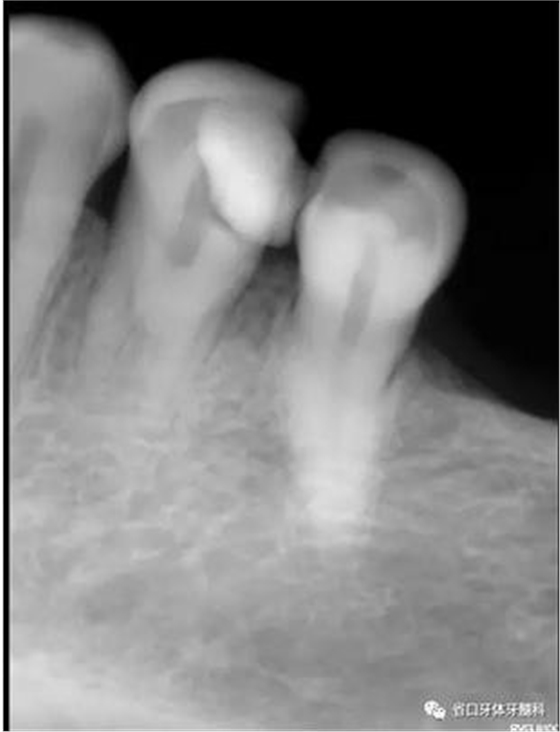

圖1:術前X線片:34遠中高密度影及髓,疑似雙根管

1、以單根管為主的下頜第一前磨牙,由于發(fā)育上的特點,根管系統(tǒng)存在較大變異,可能是最難以進行根管清潔和成型的一組牙齒,常因為忽略了雙根管及多根管的存在,造成遺漏根管發(fā)生。本病例中,34的術前X線片可見,主根管影像突然消失,提示我們可能存在多根管,CBCT的有助于我們了解根管分叉位置和根管的彎曲情況,全程顯微鏡下治療有助于我們進行髓底探查及進行有效預備根充。